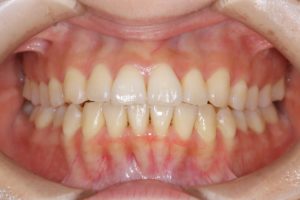

【スプリント治療前】

約4ヵ月間、就寝時にスプリント使用していただきました。

【スプリント治療後】

歯並びは変わっていませんが、顎の位置が正常に安定したことで

噛み合わせの位置が変化していることが分かります。

正しい位置で咬めるようになったためインビザラインに移行します。